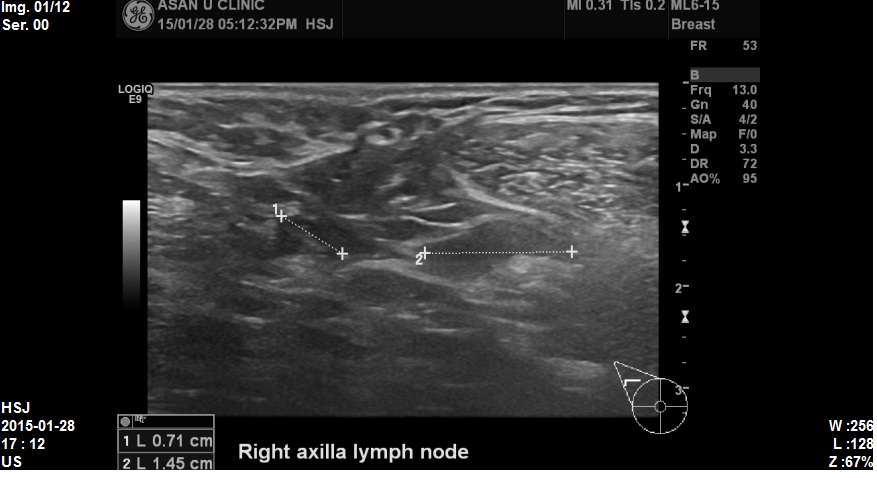

우측겨드랑이 부분초음파 다시 시행해보니

림프절 비대소견있어 세포검사를 시행하였습니다.

조직검사결과 침윤성유관암 및 겨드랑이전이로 진단되었습니다.